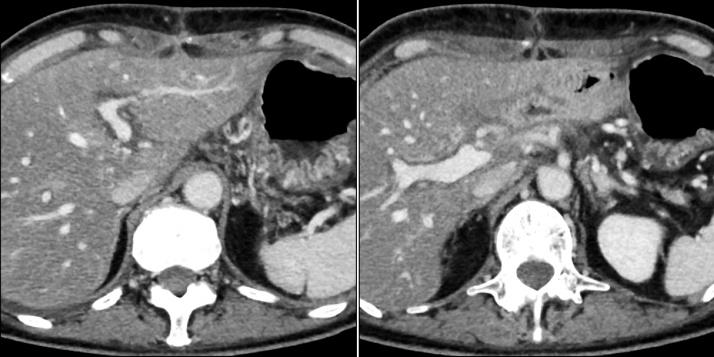

A 65-year-old woman was diagnosed with pancreas head carcinoma involving the superior mesenteric vein (SMV). Pancreaticoduodenectomy combined with SMV resection was followed by HJ. Twisting or narrowing was not evident during anastomosis. Total bilirubin values progressively increased to 13mg/dL on day 5. At that time, we suspected anastomotic occlusion and found complete portal thrombosis of the left liver. Therefore, emergency re-anastomosis of the HJ was followed by thrombectomy, which was not completely successful and did not completely recover initial portal flow. Thrombolytic drugs improved obstructive jaundice, eradicated the organized thrombosis and recovered the portal flow by day 30. The post-operative course was uneventful.

A thrombosis immediately formed in the portal vein due to biliary obstruction of an anastomotic site. We speculated that biliary dilation and related inflammation caused a relative increase in arterial flow and decreased portal flow at the localized part of the umbilical portion. Although early surgical thrombectomy was attempted soon after the primary operation, the organized thrombosis persisted. However, thrombolytic therapy eradicated the thrombosis.

一名65岁女性被诊断为胰头癌侵犯肠系膜上静脉。行胰十二指肠切除术联合肠系膜上静脉切除术后进行肝空肠吻合。吻合过程中未见扭转或狭窄。术后第5天总胆红素值逐渐升至13mg/dL。此时,我们怀疑吻合口闭塞,发现左肝门静脉完全血栓形成。因此,紧急再次进行肝空肠吻合,随后行血栓切除术,但未完全成功,门静脉血流未完全恢复。溶栓药物改善了梗阻性黄疸,消除了机化血栓,至第30天时门静脉血流恢复。术后病程顺利。

吻合口胆道梗阻导致门静脉立即形成血栓。我们推测胆道扩张及相关炎症导致脐部局部动脉血流相对增加,门静脉血流减少。尽管在初次手术后不久即尝试早期手术取栓,但机化血栓仍持续存在。然而,溶栓治疗消除了血栓。